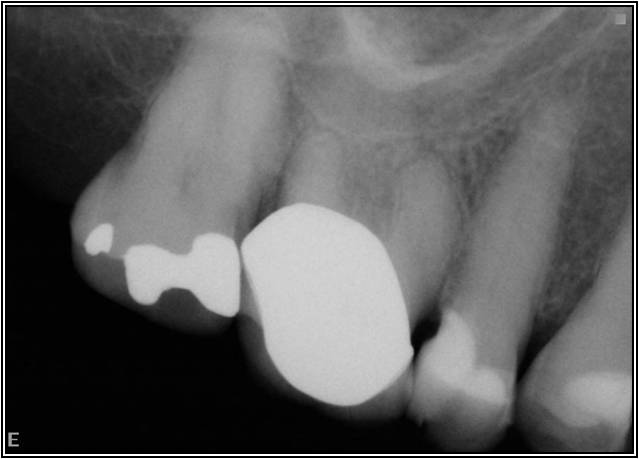

Excellent diagnosis essentially begins with two fundamental components: a doctor willing to listen to the patient’s chief complaint, and proper diagnostic tools. Among the most important tools are a precise periapical radiograph (PA) and bitewing (BW). Although a PA is often enough to provide an accurate portrayal of the patient’s condition, sometimes it alone does not suffice. Figure 1, Figure 2, and Figure 3 demonstrate a case that illustrates this point clearly. Despite two acceptable PAs (Figure 1 and Figure 2), it is difficult to assess the source of the patient’s pain to temperature. However, the BW radiograph Figure 3 provides significantly more clarity than either of the two PAs. The BW depicts localized bone loss (around tooth No. 2), a pulp stone (No. 2), a flat occlusion, numerous calcified canals, multiple restorations in tooth No. 30, and gross decay especially on tooth No. 3, which is the source of the patient’s pain to temperature. In this instance these images depict how much more useful a BW can be than just a conventional PA.

Fig 1. Foreshortened PA radiograph.

Figure 1

Fig 2. Acceptable PA radiograph.

Figure 2

Fig 3. BW of the same upper right area as shown in Figure 1 and Figure 2, depicting gross decay not visualized on prior PAs.

Figure 3